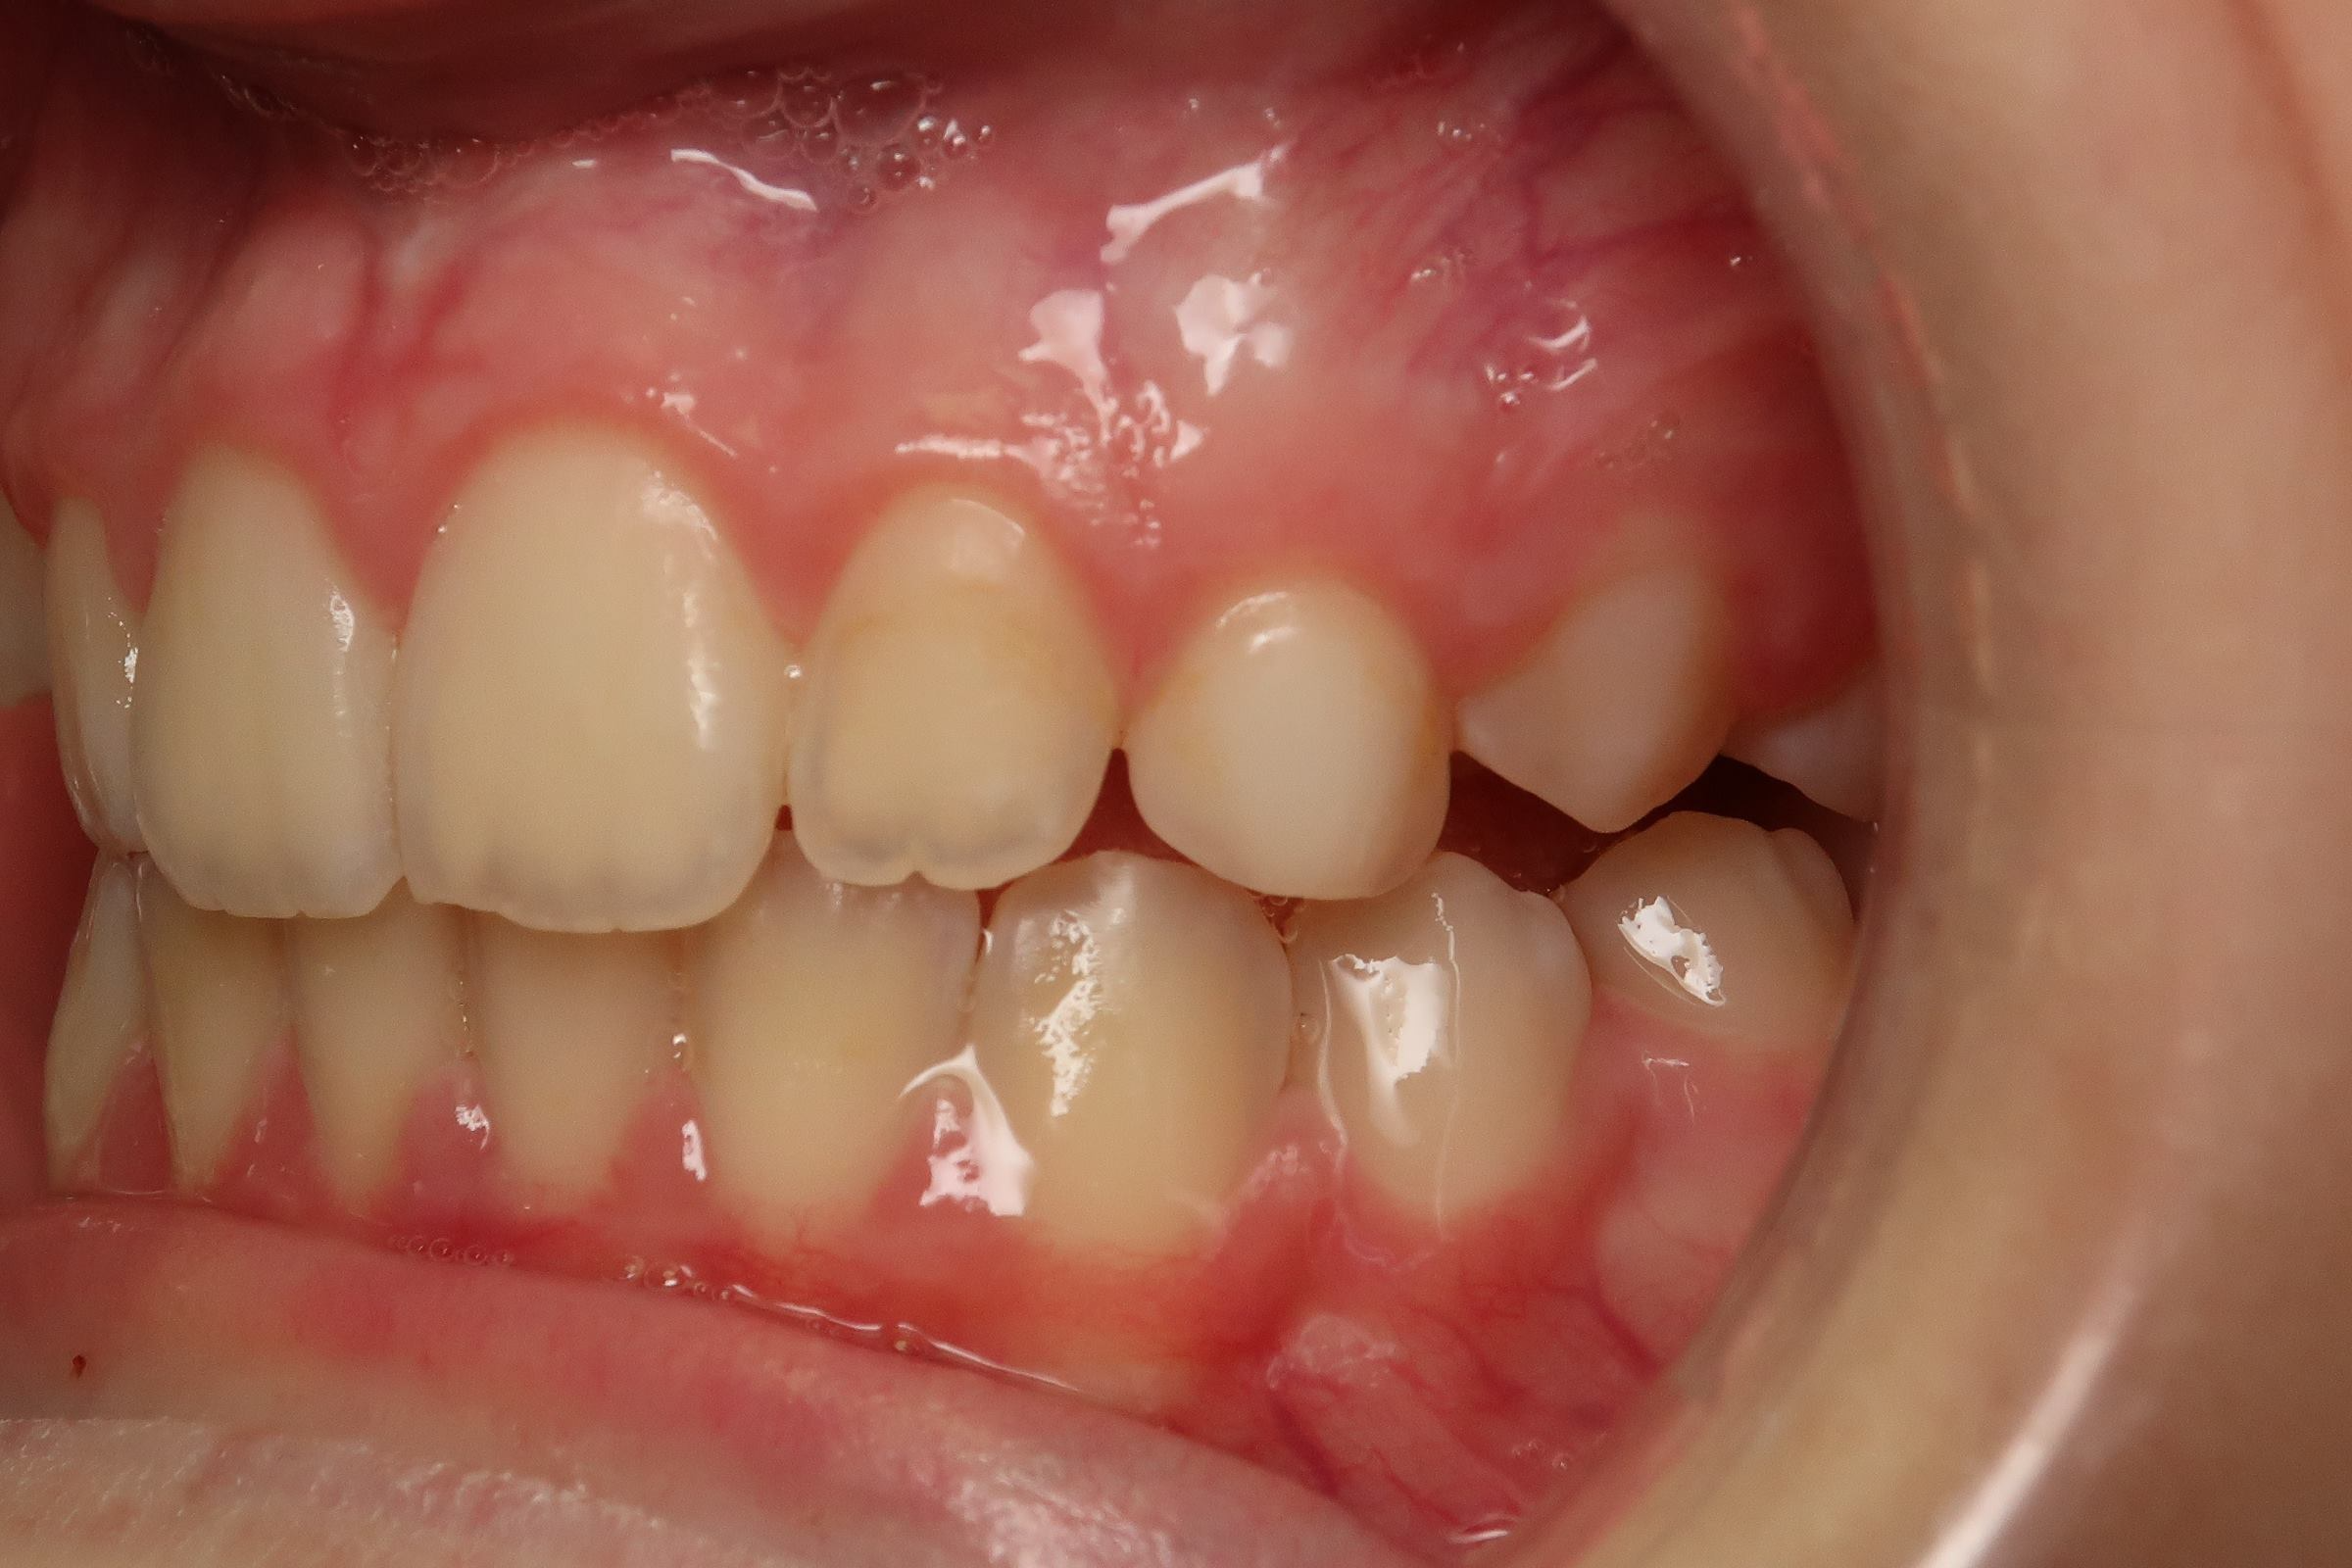

18 béance inversé droit 4 ans

inversion des dents postérieur et espace entre l'arcade du haut et du bas (béance)

bilan de début et en cours de traitement